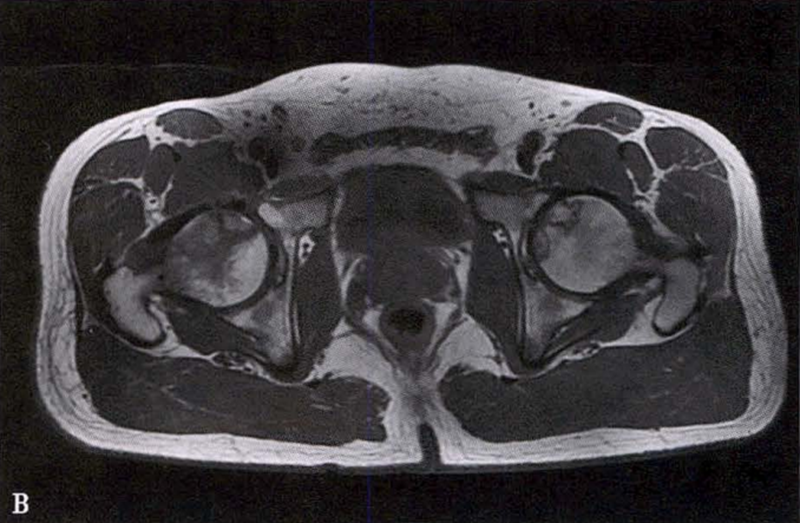

冠状面及横断面MRI图像

MRI示双侧股骨头坏死,冠状面显示右侧股骨头坏死(图A、C),横断面显示双侧股骨头坏死(图B、D);T1加权像(图A、B)显示硬化带为低信号,T2加权像(图C、D)显示右侧骨坏死硬化带外围高信号的骨髓水肿,左侧无骨髓水肿。